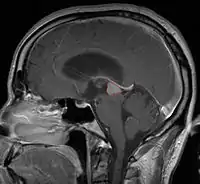

Pineal Gland Tumors

- Determined by the spatial anatomy and direction of growth

- Obstruction of aquaduct: hydrocephalus presenting as headaches, nausea, vomiting

- Compromise of superior colliculus: vertical gaze palsy, pupillary and oculomotor nerve paresis (Parinaud syndrome)

- Work-up includes MRI, CSF, serum markers for bHCG and AFP

- Usually well-circumscribed, large lesions, sometimes with cystic component